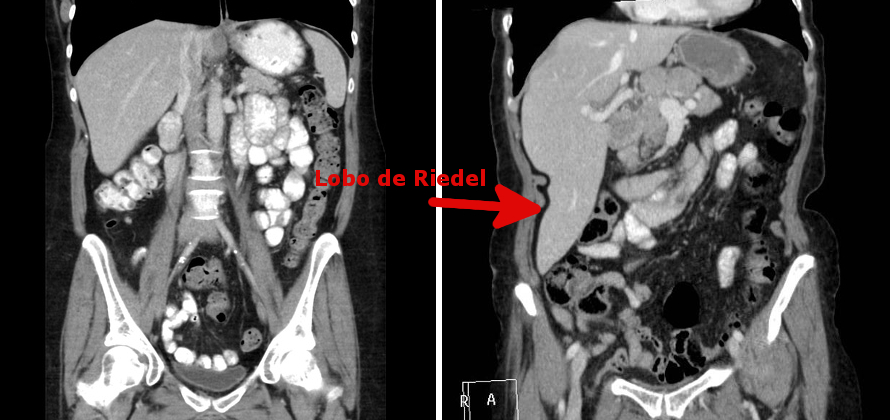

Em exames de imagem não fica mais fácil. Na falta de um método prático de calcular o volume, exames de imagem medem o fígado de vários ângulos, o que nem sempre é possível e pode levar a outros tipos de erros. Um erro comum, por exemplo, é quando o fígado tem uma variação anatômica (normal) chamada “lobo de Riedel“. Trata-se de um prolongamento afilado da borda inferior do lobo direito do fígado que ocorre em uma média de 17% das pessoas (e três vezes mais comum em mulheres do que em homens) que nem sempre é fácil de identificar no exame físico mas frequentemente é interpretado como hepatomegalia por ultrassonografistas que levam em consideração apenas a extensão do fígado.

Claro, existem protocolos bem estabelecidos para medir o volume do fígado, especialmente usando tomografia computadorizada, mas na prática isso fica reservado para avaliar compatibilidade de volume no caso de transplante hepático de doador vivo e quando se planeja retirar um tumor do fígado e é necessário estimar quanto do fígado vai permanecer e se será suficiente (nos portadores de cirrose, a capacidade de regeneração do fígado está praticamente esgotada).